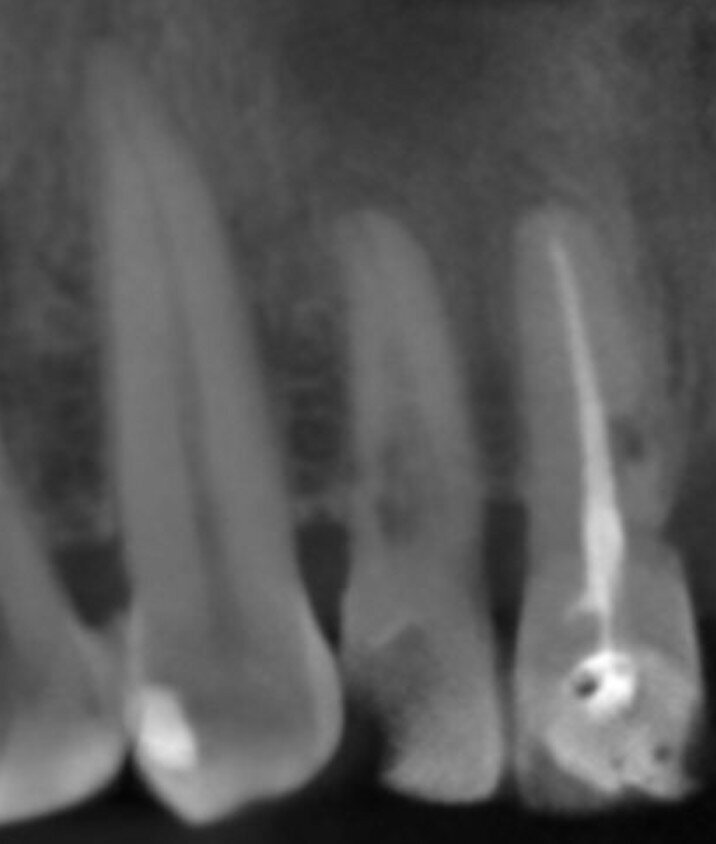

A 52-year-old man, a non-smoker in good general health, was referred after diagnosis of post-traumatic resorption affecting the roots of teeth #11 and #12 (Figs. 1a & 1b). The patient had previously consulted with an endodontist, who stated that both teeth were hopeless and therefore extractions were required. Clinical examination revealed a complete, healthy periodontium around tooth #12 with no sign of infection. At tooth #11, a slight tissue oedema associated with chronic irritation in front of the extensive resorption was observed. The intermaxillary relationship was normal, and the analysis of the smile showed a low smile line (Fig.2). Tooth #21 had been replaced by an implant-supported crown. The previously requested CBCT scan showed that the resorption process was more advanced at tooth #11 (Fig. 3).

We used the previous CBCT scan to evaluate the bone volume in the apical area of teeth #11 and #12, as well as the integrity of the buccal plate at both sites (Fig.4). The examination of the CBCT scan showed that the buccal plate was intact 3 mm below the gingival level and this correlated to the findings of the clinical examination. The future extraction sockets were determined as Class I according to Elian et al.[2]